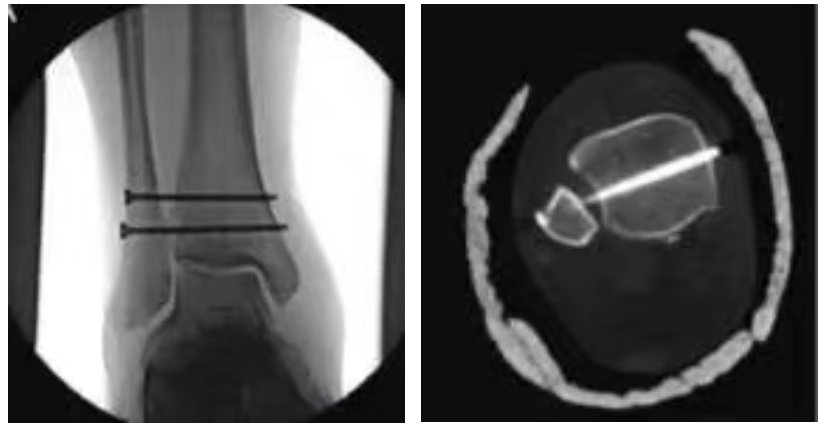

傳(chuan)統手(shou)術:剛性固(gu)定(ding)

金(jin)屬接骨(gu)螺釘固(gu)定脛骨(gu)及腓(fei)骨(gu),恢復(fu)下脛腓(fei)關節(jie)穩(wen)定性

脛腓前韌帶(dai)可逐漸(jian)瘢痕愈合

十二周(zhou)后取出接骨螺釘